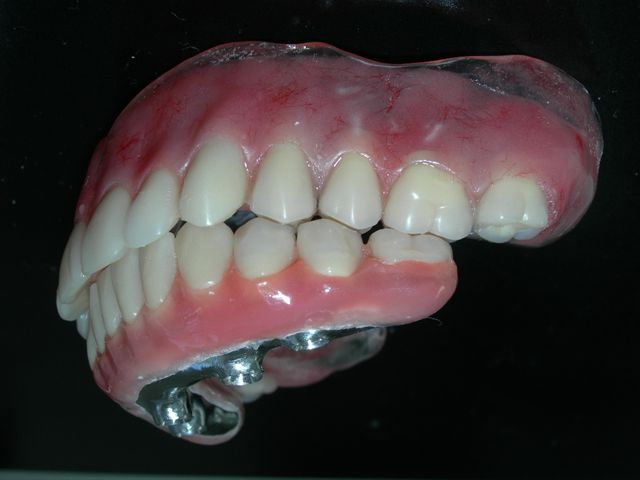

Prova de articulação pós acrilização (fase laboratorial) |

Prova de articulação após acabamento (fase laboratorial) |

Próteses antagonistas articuladas entre si sobre bancada (Vista do ângulo de insercção da prótese protocolo inferior) |